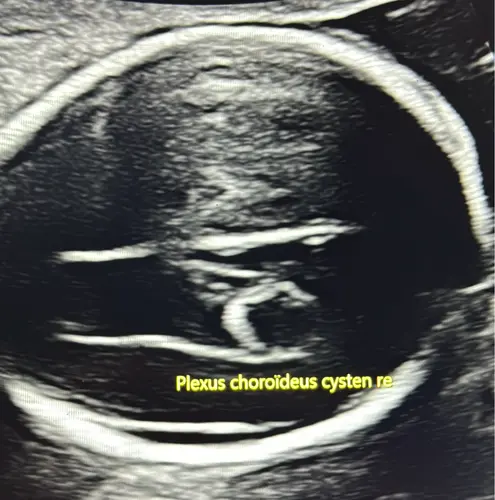

Hoi hoi!! Bij mijn vorige zwangerschap had ik dit ook bij m’n zoontje. Met nog witte darmpjes erbij dus toen moest van alles extra onderzocht worden. Syndroom van down etc. Echter waren de witte darmpjes na een weekje weg en de cyste na 4 weken als ik mij niet vergis… die cyste schijnt heel vaak voor te komen en is het maar 1 bevinding zoals bij jou, gaan ze niet verder onderzoeken heb ik begrepen. Overigens heb ik een zeer gezond jongetje van 1,5 hier rondrennen ❤️

Bij mijn vorige zwangerschap had mijn zoontje dat ook, toen zeiden ze dat ik mij geen zorgen hoefde te maken en het was met 26 weken ook alweer weg, ik weet alleen niet hoe groot het bij hem was.